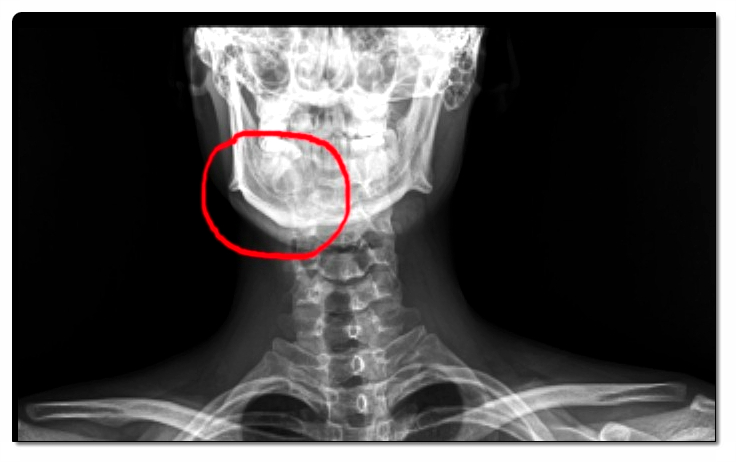

턱관절은 머리뼈와 아래턱뼈가 맞물려 움직이는 복잡한 구조입니다.

관절 내부에는 관절원판(디스크)이라는 조직이 있어 충격을 완화하는 역할을 합니다.

그런데 이 디스크가 제자리를 벗어나면 ‘딱’ 하는 소리가 나는데, 이를 정복성 관절원판 전방변위라고 부릅니다.

이 상태가 오래 지속되면 디스크가 완전히 제자리로 돌아가지 못하는 비정복성 관절원판 전방변위로 진행될 수 있습니다.

이때는 입이 잘 벌어지지 않거나 통증이 심해지기도 합니다.

턱관절은 머리와 척추를 이어주는 중요한 축입니다.

턱 정렬이 틀어지면 목, 어깨, 척추까지 영향을 미치게 됩니다.

턱관절 문제로 인한 근육 긴장은 두통, 어깨 결림, 귀 주변 통증으로 이어질 수 있습니다.